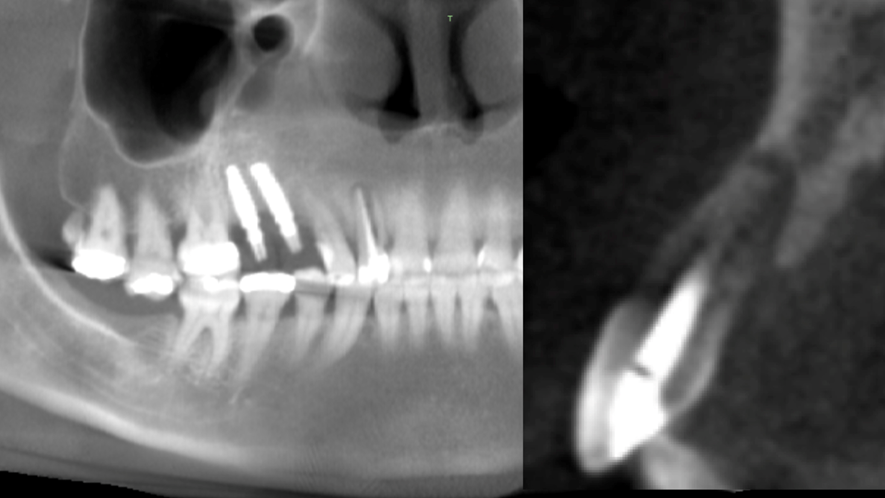

Este trabalho tem como objetivo relatar um caso clínico de exodontia minimamente invasiva de um incisivo lateral superior com fratura radicular, realizando implante imediato em alvéolo pós-extração, enxerto de tecido conjuntivo subepitelial e osso bovino liofilizado para preenchimento de GAP, prontamente à instalação de pilar reto e provisório imediato.